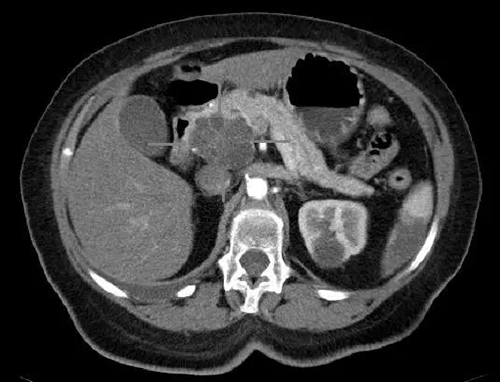

胰头癌和囊腺癌具有iv比照度的轴向CT图像(图片泉源:Science)

美国癌症协会预计�,�,每年在美国有快要 60,000 人被诊断患有胰腺癌�,�,其中近 50,000 人死于这些癌症�。�。�。�。�。�。胰腺癌的治愈率很是低�,�,主要是由于这些癌症往往仅在晚期最先在体内扩散时才被发明�,�,并且对化学疗法和其他疗法具有相对的对抗力�,�,因此迫切需要更好的胰腺癌治疗要领�。�。�。�。�。�。

胰腺癌、胰管腺癌或 PDAC 是最常见的形式�,�,通常具有部分删除 17 号染色体的特征�。�。�。�。�。�。人类细胞具有 22 对染色体以及X和Y性染色体�。�。�。�。�。�。在 PDAC 中丧失了第 17 号染色体一个拷贝的一部分�,�,意味着位于该染色体上的许多基因仅剩下一个拷贝�,�,因此这些基因编码的卵白质水平降低了�。�。�。�。�。�。这最终会增进受影响的癌细胞的生长�,�,部分缘故原由是受影响的卵白质之一是肿瘤抑制物 P53�,�,它通�??�?勺魑渴⒌墓收锨寰部�,�,避免细胞太过破碎�。�。�。�。�。�。